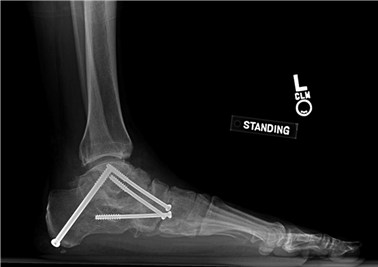

The Lapidus Arthrodesis (First TMT Fusion)

For severe deformities or hypermobility, the Lapidus procedure provides robust stabilization of the medial column. A dorsal or medial incision is utilized over the first TMT joint. The extensor hallucis longus (EHL) is retracted dorsally, and the tibialis anterior tendon is identified and protected at its insertion on the medial cuneiform and first metatarsal base. The TMT joint capsule is incised, and the joint is thoroughly debrided of all articular cartilage using a combination of osteotomes, curettes, and a high-speed burr.

To achieve multiplanar correction, the surgeon must address the sagittal, coronal, and transverse planes. The first metatarsal is plantarflexed to restore the longitudinal arch, rotated out of pronation to realign the sesamoids, and translated laterally to close the IMA. Subchondral drilling or feathering is performed to optimize the biological environment for fusion. Fixation is traditionally achieved with two or three crossed solid or cannulated screws (typically 3.5mm or 4.0mm). Recently, plantar or medial locking plates have gained immense popularity due to their superior biomechanical construct, allowing for earlier weight-bearing. Bone graft or orthobiologics may be packed into the arthrodesis site to stimulate osteogenesis.

Image

During this phase, patients transition to a Controlled Ankle Motion (CAM) boot. For distal osteotomies, progressive weight-bearing to tolerance is permitted. Crucially, active and passive range of motion (ROM) exercises of the first MTP joint are initiated to prevent capsular adhesions. The patient is instructed to manually plantarflex and dorsiflex the hallux multiple times daily. For Lapidus patients, NWB is generally maintained until 4 to 6 weeks, though recent literature utilizing robust plantar plating constructs has pushed for earlier protected weight-bearing. Radiographs are obtained at 6 weeks to assess for early callus formation and maintenance of alignment.

Phase 3: Transition and Strengthening (Weeks 6 - 12)